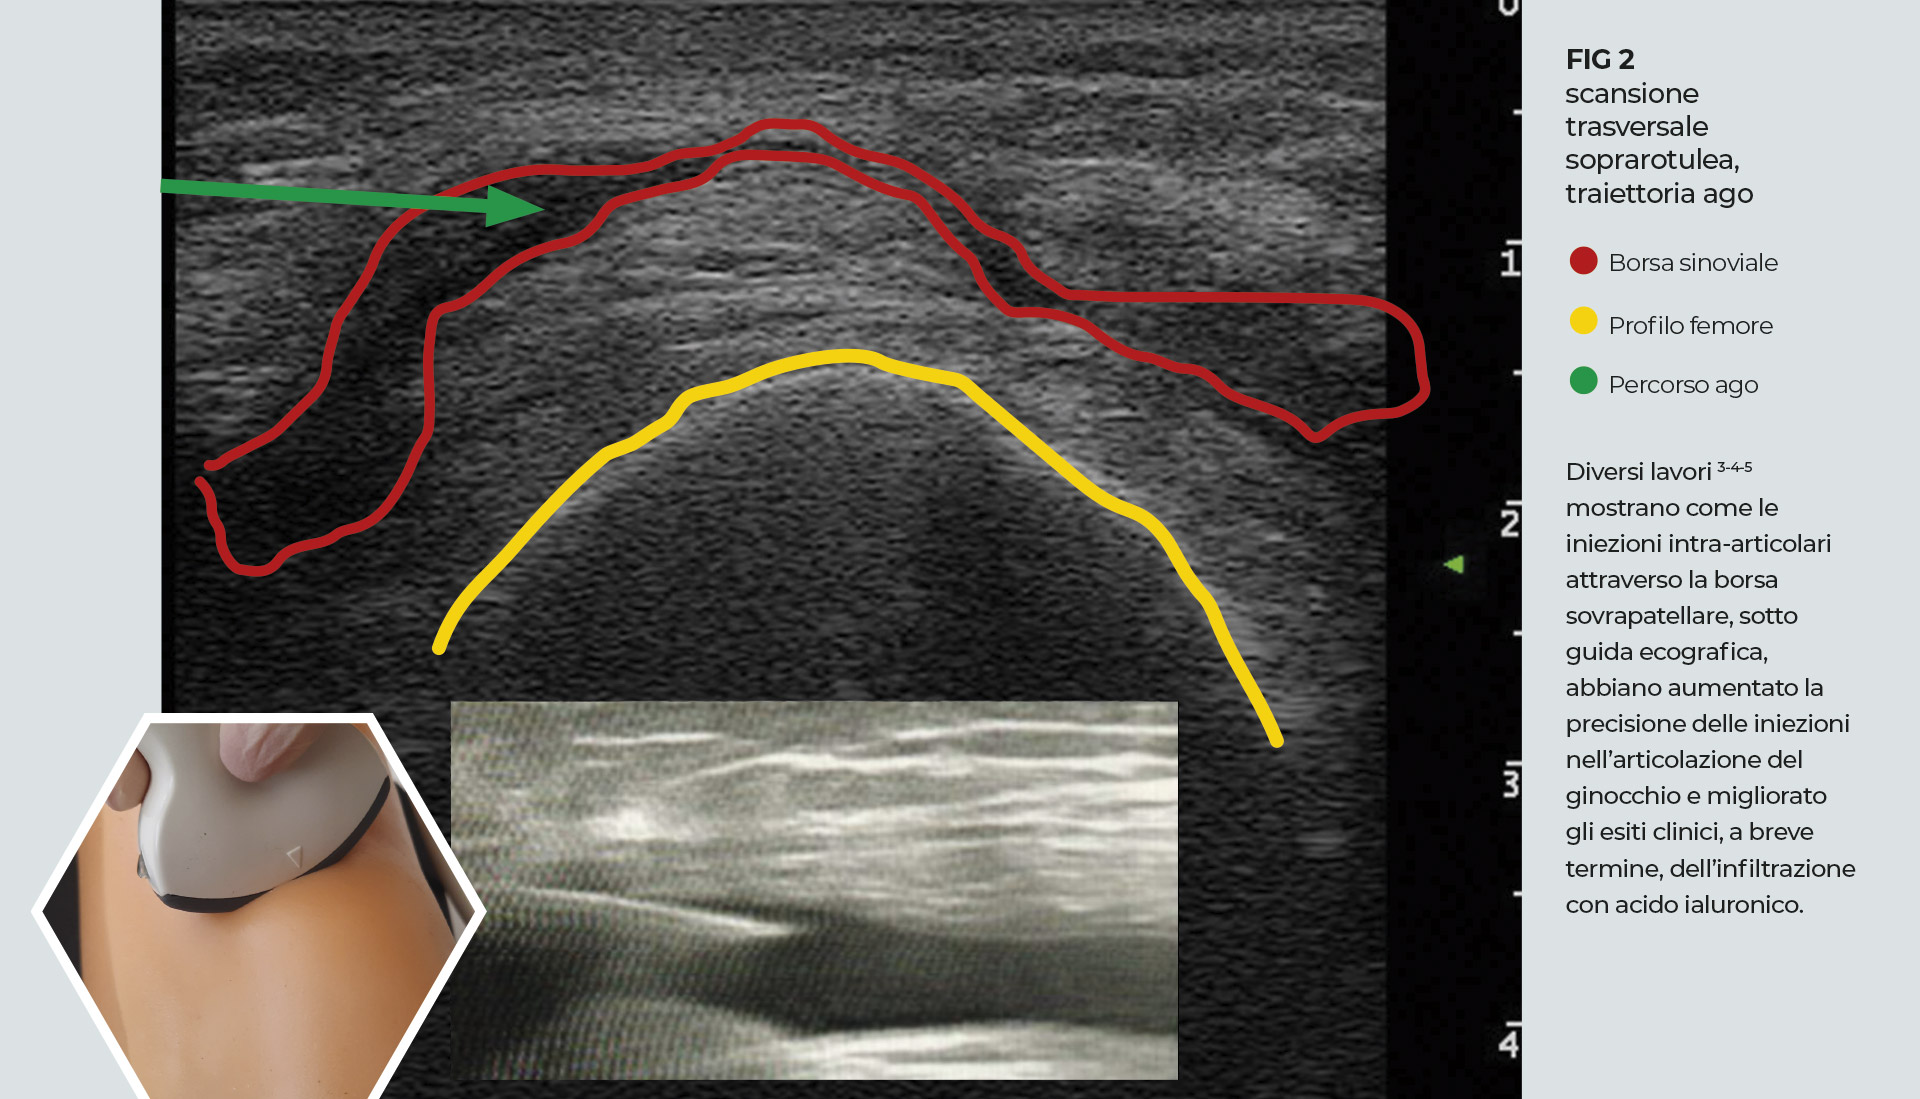

Identificato il recesso sinoviale si ruota la sonda di 90° con una scansione trasversale del recesso, al di sopra della corticale del femore. Identificato il punto di iniezione laterale, sottorotuleo, parallelo all’asse maggiore della sonda, si pratica l’iniezione con ago 21/22 G, guidati dalla visualizzazione ecografica dello stesso e dal rigonfiamento della borsa conseguente all’introduzione del farmaco iniettato. Importante stabilizzare la sonda con le dita della mano che la manovra a contatto con la pelle, evitare una pressione eccessiva da parte della stessa ed eseguire piccoli movimenti.

3. J Clin Ultrasound. 2012 Jan;40(1):20-5. Accuracy of blind versus ultrasound-guided suprapatellar bursal injection Yong Bum Park et Al.

4. Int J Rheum Dis. 2018 Jan;21(1):134-139. A randomized blinded comparative study of clinical response to surface anatomy guided injection versus sonography guided injection of hyaloronic acid in patients with primary knee osteoarthritis. Kianmehr N. et Al.

5. Arthroscopy, Sports Medicine, and Rehabilitation, Vol 3, No 4 (August), 2021: pp e1177-e1187 Ultrasound-Guided Knee Injections Are More Accurate Than Blind Injections: A Systematic Review of Randomized Controlled Trials William H. Fang et Al.